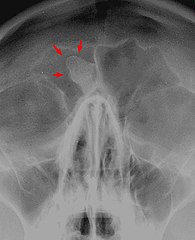

Рентгенологическая диагностика остеомы лобной пазухи: что нужно знать при исследовании

При подозрении на остеому лобной пазухи важно выполнить рентгеновское исследование, чтобы точно определить её локализацию и размер.

Рентгеновские снимки могут помочь выявить плотные участки в области лобной пазухи, что является характерным признаком остеомы.

Остеома лобной пазухи

Для более точной диагностики рекомендуется делать рентген в нескольких проекциях — это позволит получить полное изображение структуры пазухи.

Рентгеновские снимки лобной пазухи могут помочь отличить остеому от других заболеваний, таких как синусит или кистозные образования.